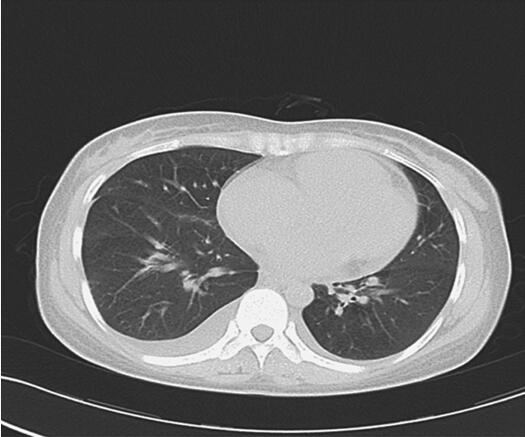

诊治经过:入院后查血常规示:WBC 11.3×109/L,N 77.3%,Hb 127g/L,PLT 202×109/L;生化:LDH 545IU/L,Ca2+ 1.9mmol/L,余未见异常;cTnI 0.20ng/ml,BNP 1315pg/ml;凝血:PT 15.4秒,APTT 36.5秒,INR 1.28,FIB 4.1g/L,D-二聚体0.93μg/ml;抗“O”47.5IU/ml;血沉:5mm/h,入院后第1天予青霉素、异帕米星联合抗感染,硝酸甘油、利尿剂减轻心脏负荷,营养心肌等治疗。入院第3天查肺部CT(图38-1),入院第4天查心脏彩超(图38-2)。入院第5天请心外科会诊,转心外科手术治疗。入院第8天在全麻CPB下行“左心房黏液瘤切除术”。手术顺利,术后继续给予阿莫西林-舒巴坦钠抗感染、营养心肌等对症处理,患者恢复顺利,复查血常规、生化大致正常,复查心电图、胸片未见明显异常,入院后第15天复查心脏彩超示左心房黏液瘤术后,左心房内未见异常征象,二尖瓣反流(+~++),心包少量积液。病理如图38-3。入院第17天出院。但该患者出院后肿瘤复发,术后半年内死亡。

图38-1 胸部CT示双肺感染,双侧胸腔少量积液,右上肺局限性肺气肿

3.血象高,肌钙蛋白、BNP升高,胸部CT示双肺感染,双侧胸腔少量积液,右上肺局限性肺气肿。